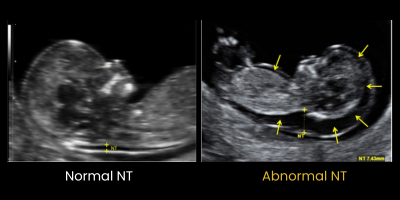

- Fetal Nuchal Translucency (NT)

Fetal Nuchal Translucency (NT) Scan in Gwalior

What is an NT Scan?

A Fetal NT Scan in Gwalior, also known as a Fetal Nuchal Translucency Test, is an ultrasound performed between 11 and 14 weeks of pregnancy (first trimester).

This scan measures the fluid-filled space at the back of your baby’s neck, known as nuchal translucency, to assess the risk of chromosomal abnormalities such as Down syndrome.